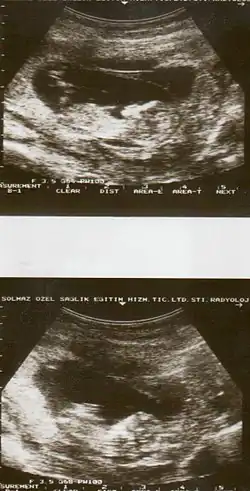

![]() | |

| Drawing of internal and external bleeding from placental abruption | |

| Diagnostic method | Based on symptoms, ultrasound[1] |

The cause of placental abruption is not entirely clear.[2] Risk factors include smoking, pre-eclampsia, prior abruption (the most important and predictive risk factor), trauma during pregnancy, cocaine use, and previous cesarean section.[2][1] Diagnosis is based on symptoms and supported by ultrasound.[1] It is classified as a complication of pregnancy.[1]

Placental abruption is suspected when a pregnant mother has sudden localized abdominal pain with or without bleeding. The fundus may be monitored because a rising fundus can indicate bleeding. An ultrasound may be used to rule out placenta praevia but is not diagnostic for abruption.[8] The diagnosis is one of exclusion, meaning other possible sources of vaginal bleeding or abdominal pain have to be ruled out in order to diagnose placental abruption.[5] Of note, use of magnetic resonance imaging has been found to be highly sensitive in depicting placental abruption, and may be considered if no ultrasound evidence of placental abruption is present, especially if the diagnosis of placental abruption would change management.[16]